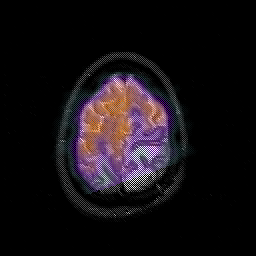

Glioblastoma multiforme overlay -- Slice #44

[Home][Help][Clinical][Tour 1][Tour 2][Tour 3] Slice 44